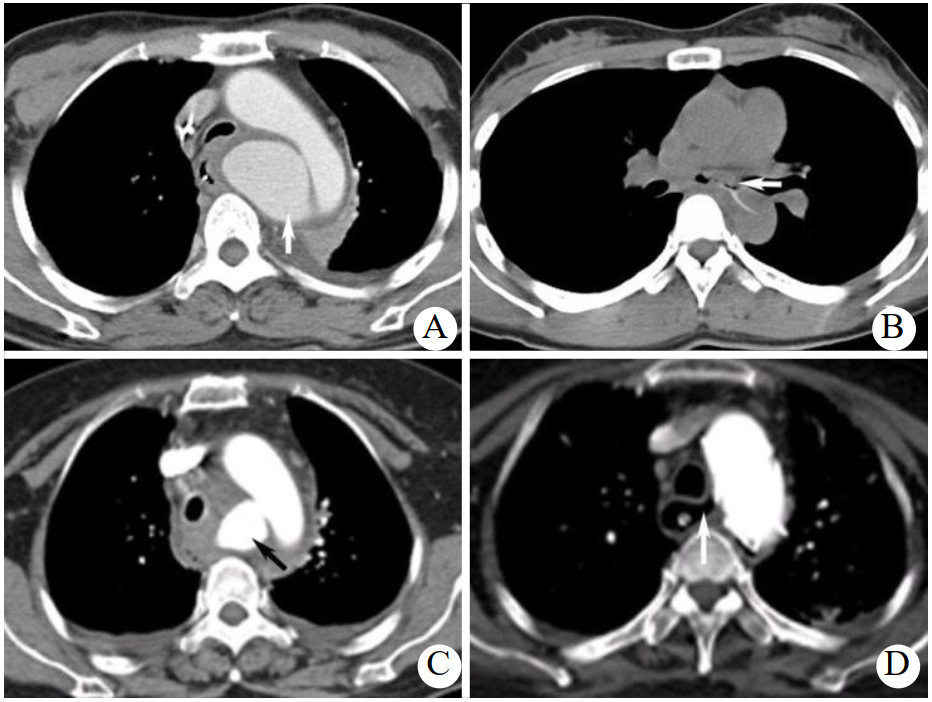

1 资料与方法病例1,女,53岁,1周前有鱼刺吞咽史,吞咽有异物感、伴疼痛,无呕血、黑便等情况。CT提示食管周围渗出伴气体影,考虑食管穿孔并发周围脓肿。胃镜示距门齿25 cm食管前壁可见0.5 cm缺损,周边黏膜充血水肿,未见明显异物。血常规提示白细胞及中性粒细胞百分比明显升高。入院后予禁食、广谱抗生素抗感染、营养支持等治疗。1周后患者突发大量呕血,胃镜示距门齿20~25 cm食道前壁一突向食道腔血肿。增强CT示主动脉弓内后方假性动脉瘤形成(图 1A)。考虑发生AEF。因患者有休克表现,急诊行主动脉腔内覆膜支架植入(thoracic endovascular aortic repair, TEVAR)。术后继续抗感染4周,复查CT提示假性动脉瘤消失、纵隔感染控制,随访3年无并发症后失访。

| A: 患者1增强CT显示主动脉弓内后方假性动脉瘤形成(箭头示);B: 患者2 CT平扫显示食管内异物刺穿食管壁,向左后刺入胸主动脉(箭头示);C:患者3 CTA显示主动脉弓假性动脉瘤形成(箭头示);D:患者3 CTA可见明显的AEF存在,瘘管非常清晰的与TEVAR术后的主动脉相连(箭头示) 图 1 三例患者增强CT结果 |

病例2,女,31岁,2 d前进食鱼肉后出现胸骨后吞咽疼痛,无发热、呕血等不适。胃镜示距门齿30 cm处一鱼刺样异物刺入食管壁。CT示气管分叉下方水平见一条状高密度影,向左后刺入胸主动脉,邻近纵隔内少许积气,邻近食道周围渗出改变,结合病史考虑食道内异物(鱼刺)刺入胸主动脉出现AEF(图 1B)。患者行急诊开胸手术,取右侧卧位股动静脉插管建立体外循环,打开纵隔胸膜后发现一枚2 cm左右长的锋利鱼刺刺破隆突下2 cm处食道左侧壁后刺入主动脉,未见明显脓肿形成,组织活力尚好。清除鱼刺、消毒冲洗后直接修补主动脉穿入点,同时以食管周围组织瓣缝合修补食道瘘口。胸腔手术完成后转平卧位行腹腔镜下空肠造瘘。患者术后恢复平稳,随访5年后失访。

病例3,女,56岁,1周前鱼刺伤、3 d前高热39 ℃伴频发呕鲜血入院。断层摄影血管造影(computed tomography angiography,CTA)示食管异物伴穿孔,主动脉弓假性动脉瘤形成(图 1C)。患者大出血后循环不稳定,急诊行TEVAR术控制出血,术毕造影无内漏,胃镜下再取出鱼刺。术后持续广谱抗生素抗感染、禁食、空肠置管营养支持。患者家属始终无法决定行开放手术彻底解决AEF。术后2个月复查CTA提示纵隔感染控制良好。食管造影及胃镜示瘘口愈合,患者恢复进食。术后7个月,患者因突发大量呕血再至本院,出现血压下降、昏迷等休克症状,立即予复苏抢救,胃镜示距门齿22 cm食管壁可见一占位,表面溃疡、糜烂伴出血,结合既往病史考虑原有食管瘘口再次破裂。经积极治疗后患者病情稳定。复查主动脉CTA可见明显的AEF存在,瘘管与TEVAR术后的主动脉明显相连(图 1D)。胃镜见距门齿23 cm处食管瘘口,并见TEVAR支架裸露。此后18个月患者在门诊复查数次CTA及胃镜均无明显变化。患者于术后27个月因发热再次入院,CTA示主动脉弓水平纵隔感染较前明显加重,经抗感染等治疗病情稳定后再次建议患者开放手术治疗未果,患者出院数个月后死亡。